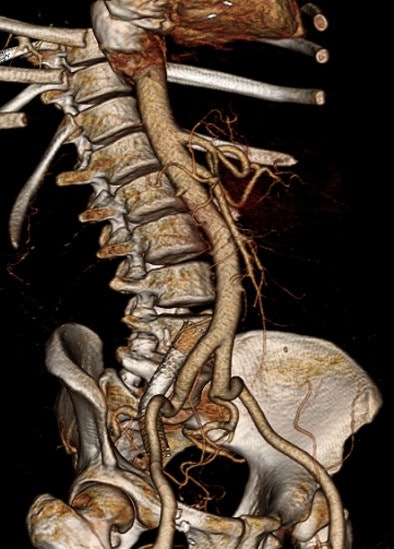

| Patient is in renal failure but not yet on dialysis. CTA was acquired at 80 kVp and 360 mAs following administration of 50 mL of 350 mg/mL contrast. Contrast density in the iliac arteries is > 400 HU. Radiation dose is 4.3 mSv. There is an incidental right iliac venous stent. Images courtesy of Dr. Barry Daly. |